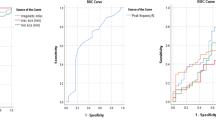

The M-P values for IACs were higher than those for PIAs (p = 0.001), with an area under the curve (AUC) of 0.810 and a threshold of 489.5 Hounsfield units (HU) in ROC analysis. The V(M-P) values for IACs were smaller than those for PIAs (p = 0.04), with an AUC of 0.805 and a threshold of 11.01 HU/day.

ROC analysis of M-P and V(M-P) for differentiating between PIA and IAC

The ROC evaluation showed areas under the curve (AUCs) for the M-P (0.810) and V(M-P) (0.805) values. The optimal cut-off points were defined as those closest to the upper left-hand corner of the curves [12], yielding thresholds of 489.5 HU and 11.01 HU/day for the M-P and V(M-P) parameters, respectively (Fig. 6). The sensitivities and specificities for the M-P values were 0.771 and 0.883 respectively, and those for the V(M-P) values were 0.500 and 0.971 respectively. Additionally, the Spearman correlation analysis for datasets with non-normal distributions, showed a significant (p = 0.001) positive correlation (0.856) between the M-P parameter and the GGN TV in the PIA group (Fig. 7).

Receiver operating characteristic curves (ROC) of the differences between the maximum and peak CT numbers (M-P) and the mean changes in velocity of the M-P (V. (M-P)) of ground-glass nodules (GGNs) for differentiating between pre-invasive adenocarcinomas (PIAs) and invasive adenocarcinomas (IACs). Areas under the curves (AUC) for M-P and V. (M-P) were 0.810 and 0.805 respectively, including a relatively good sensitivity and specificity for differentiating the threshold values of 489.6 Hounsfield units (HU) and 11.01 HU/day respectively

Malignant cells in IACs proliferated from multiple points throughout the nodule, invading the interstitium and filling it with mucous and isolated tumor cells so that, over time, the main part of the GGN showed an increasing density rather than only a solid core. Consequently, the V(M-P) values for IACs are remarkably smaller than those for PIAs, over the duration of the follow-up interval. An AUC of 0.805 was obtained, using the ROC assessment, for V(M-P) values allowing a differential diagnosis between PIAs and IACs, with a threshold of 11.01 HU/day. Accordingly, during the follow-up, if a GGN V(M-P) value larger than 11.01 HU/day is observed, PIA would be strongly suggested, rather than IAC.